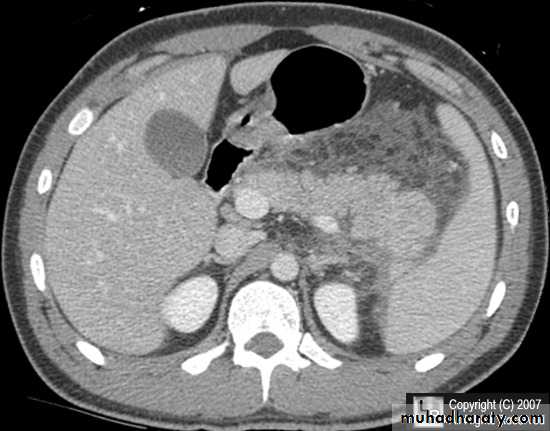

Pancreatitis

Patient present with abdominal pain , vomiting with or without jaundice , increase amylase levelCT finding

Enlargement of the pancreas focal or generalized increase in size .

Hypo density within the pancreas focal or generalized due to the edema .

Peri pancreatic fluid collection & edema around the pancreas .

The fluid around the pancreas if persist more than 6 w become encysted leading to the pancreatic pseudo cyst any area could be affected .